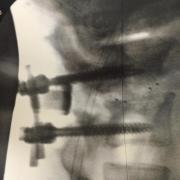

"Снимок моей поясницы, в которую доктор вставил два винта. Эта боль, от которой не спасает даже морфий, хочется застрелиться. Я попросил Кори прочитать мне молитву, только так мне удалось уснуть. Скоро я вернусь в зал и все снова будет "lightweight baby"